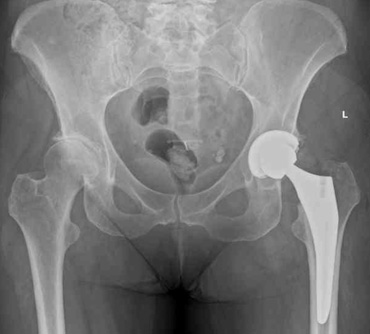

Robotic assisted hip replacement

Jon Conroy Orthopaedics uses state-of-the-art robotic assistance aids to ensure consistent and accurate positioning of implants.This accurate placement is predicted to give optimal performance of your new joint replacement. Our aim is to give you the best functional outcome and longevity for your hip or knee replacement.

The state-of-the-art Mako™ robotic arm system works alongside the surgeon from the pre-surgery planning stage through to assisting in the surgery itself in order to improve the accuracy and precision of the procedure.

Mr Conroy generally uses Stryker products including the uncemented Accolade II / Trident or cemented Exeter hip replacement.